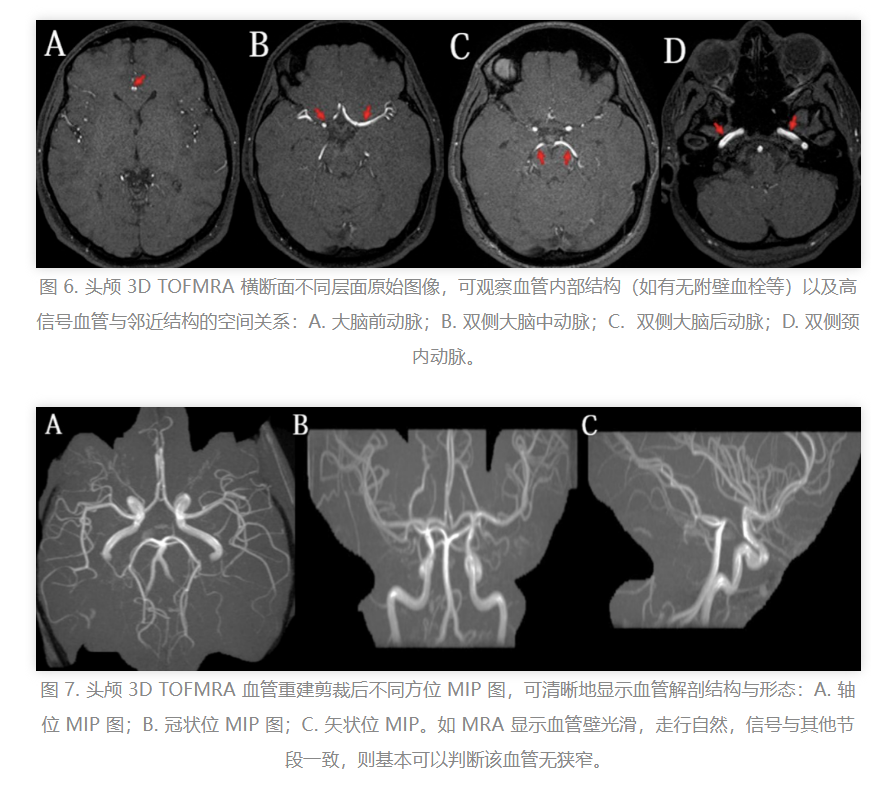

磁共振血管造影(MRA)图像的解析相对直观,主要涵盖两个方面:横断面MRA原始图像以及重建的最大信号强度投影(Maximum Intensity Projection,MIP)图像。在MRA原始图像中,血管呈现为高信号强度区域。随后,通过应用重建算法,将原始图像转换为MIP图像,该过程涉及图像的剪辑和处理。最终,MIP图像将根据不同的视角进行旋转展示。

鉴于脑血管分支的复杂性和走行的曲折性,单一视角无法全面展现其结构,因此必须选择恰当的视角和方位进行图像旋转,以确保血管结构的完整显示。

综上所述,MRA在颅内血管疾病的筛查和诊断中具有不可忽视的价值。MRA图像包括原始图像和最大强度投影(MIP)图像,临床实践中应将两者结合使用。在MIP图像发现病变后,必须仔细观察原始图像,以避免误诊或漏诊的情况发生。